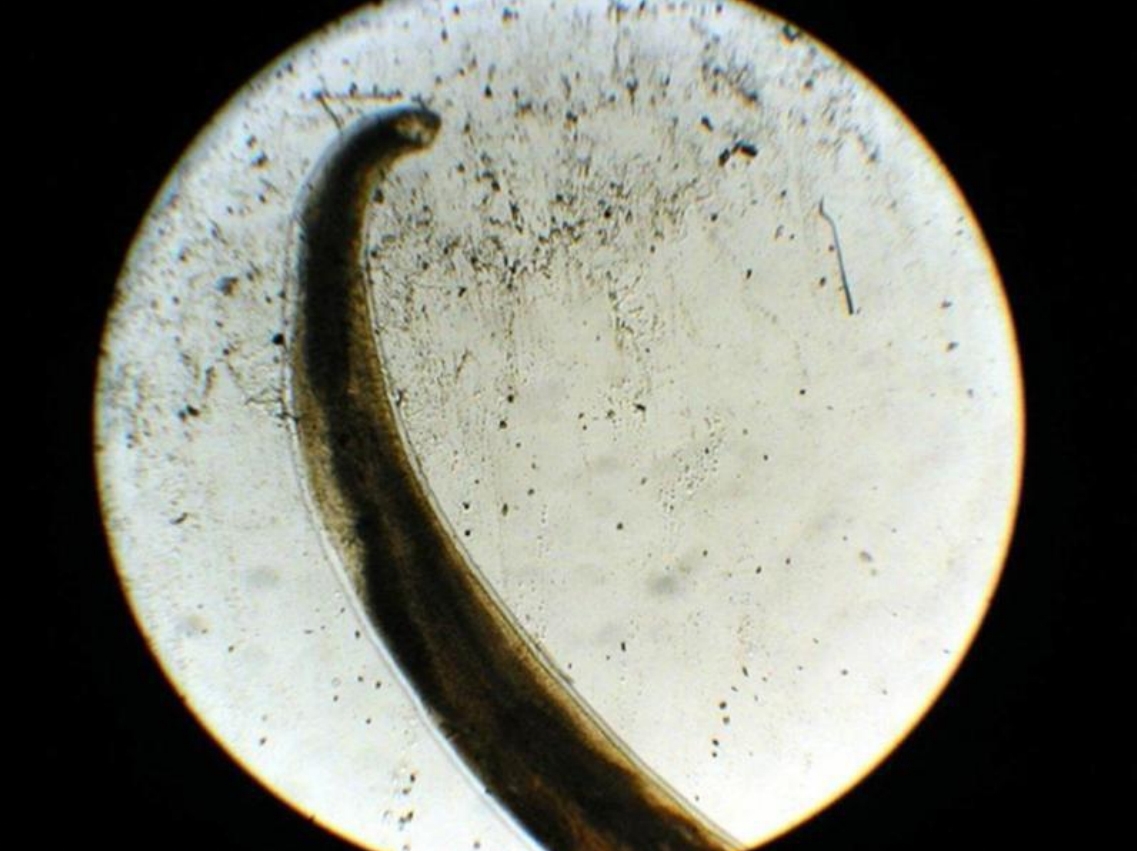

Strongyloides stercoralis 1st stage rhabditiform larva (diagnostic stage)